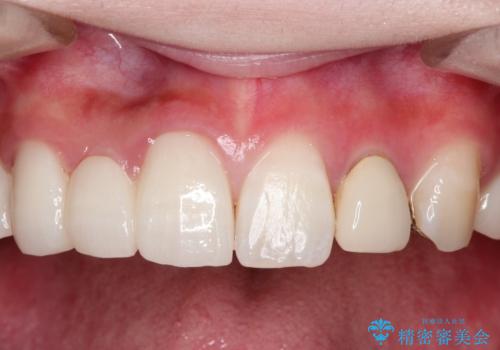

前歯にレジン前装冠(保険内)が装着されており、自然な透明感がありません。

オールセラミックによるやりかえを行いました。

色調もまわりの歯に合わせて、形態も患者様のご希望に沿うように製作させていただきました。